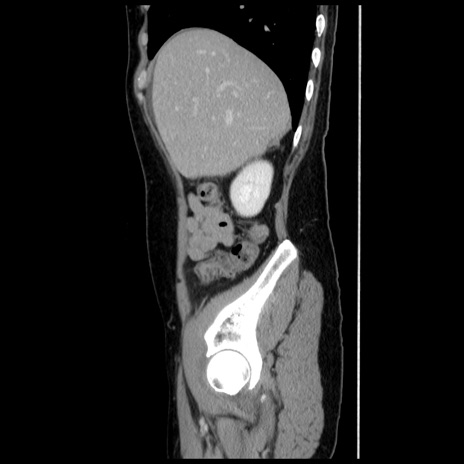

症例10(矢状断像)

【症例】 50歳代女性

【主訴】 腹痛

【現病歴】前日生レバーを食べた。今朝に排便あり。 昼前に突然発症の腹痛を生じ、当院救急外来を受診した。

【既往歴】 子宮筋腫にてで子宮全摘後

【身体所見】 意識清明、腹部:平坦、軟、下腹部やや左を中心に圧痛・反跳痛あり、筋性防御あり

【データ】WBC 7800、CRP 0.07